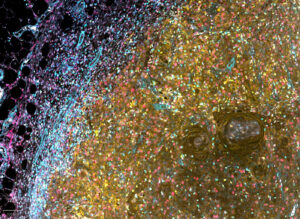

Castle Biosciences’s TissueCypher spatial proteomics platform helps address this gap by identifying high-risk biological signals that may be present before cancer develops. “Measuring proteins within their spatial context in tissue makes it possible to detect subtle, complex patterns of disease biology that cannot be captured through traditional microscopy or bulk molecular tests alone,” notes Critchley-Thorne.

The TissueCypher test employs multiplex immunofluorescence, which utilizes antibodies labeled with fluorophores to simultaneously detect multiple markers. The patient’s tissue is labeled with fluorescent tags for nine protein biomarkers and then digitally imaged. These nine protein biomarkers are associated with key pathways in the neoplastic progression to esophageal adenocarcinoma—including tumor suppression, cell cycle control, angiogenesis, and immune cell infiltration.

The platform uses AI-driven recognition to identify relevant Barrett’s tissue and remove artifacts in tissue sections or slide mounting media. This is followed by image analysis to assess how proteins and cells are organized and interacting within the tissue.

Ultimately, the spatially resolved measurements are combined into a fixed algorithm that generates a risk score, placing patients into risk categories (high, intermediate, or low), and estimating the probability of disease progression to esophageal cancer over five years. Castle delivered more than 39,000 test reports in 2025.

Discovery’s multiplexed panels enable analysis of spatial distribution patterns within the tumor microenvironment—such as the localization of lymphocytes, myeloid cells, fibroblasts, and vessels. They also elucidate key pathways in cancer progression, including changes in the migratory and invasive properties of cells, says Juncker-Jensen.

“Say you need to co-localize five transcripts, seven proteins, and several glycans and lipids within the same tissue region, organized by their spatial relationship to one another. That multi-omic biomarker composite may define a disease state much more precisely than any single layer. Our platforms support exactly that kind of investigation.”

Easterling recounts a collaboration with Stanford University and the Medical University of South Carolina to spatially localize glycans in different tissues. This information was then combined with spatial transcriptomics and proteomics layers to analyze gliomas, a lethal cancer with very limited treatment options. Ultimately, the glycomics information emerged as the strongest classifier of tumor grade across all three omics layers.